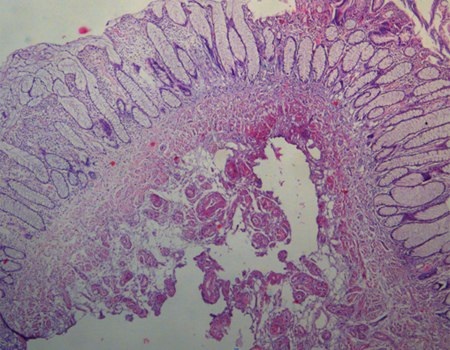

Trước khi nhập viện, bệnh nhân P.T.H, 78 tuổi bị đau bụng, tiêu lỏng trong vài tháng. Tuần trước, bệnh nhân bắt đầu đi cầu có lẫn máu nên đi khám bệnh, nội soi ruột già phát hiện khối u như trên. Sau khi thực hiện thủ thuật thành công, bệnh nhân được xuất viện ngay trong ngày và sức khỏe ổn định, sinh hoạt bình thường. Kết quả sinh thiết (nhìn dưới kính hiển vị) cho thấy toàn bộ khối u đã được cắt bỏ tận gốc. Đây là khối u lành hoàn toàn, không có hiện diện của tế bào ung thư.

Khối u được cắt nhỏ ra và soi qua kính hiển vi, thấy rõ tận phần gốc của khối u